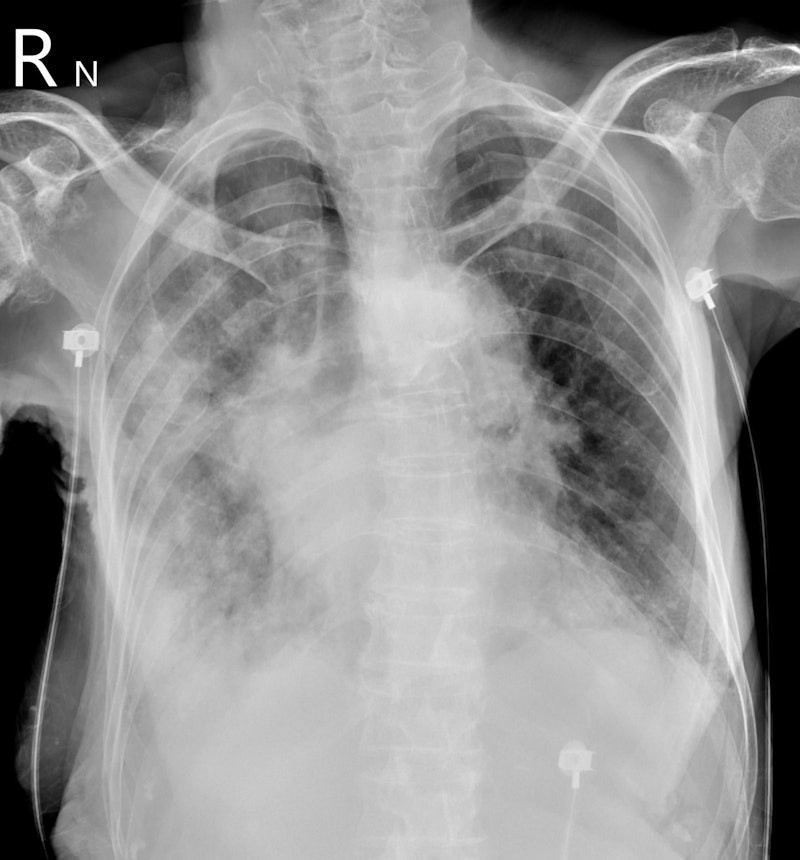

Bên cạnh đó, nhiều thông tin cho biết, khi tình trạng của Từ Hy Viên trở nặng, kết quả chụp CT cho thấy cả hai lá phổi của Từ Hy Viên đã trắng xóa. Không lâu sau, cô trút hơi thở cuối cùng.

Ngày 5/2, bác sĩ Tô Nhất Phong, chuyên khoa lồng ngực tại chi nhánh Dương Minh của Bệnh viện Thống nhất thành phố Đài Bắc (Đài Loan, Trung Quốc), giải thích rõ hơn về tình trạng "lá phổi trắng" của nữ diễn viên xấu số.

Theo bác sĩ này, "phổi trắng xóa" thực chất phản ánh tình trạng viêm phổi nặng dẫn đến khó thở.

Khi viêm phổi nặng xảy ra, phế nang sẽ chứa đầy đờm và nước bị viêm. Khi phế nang phủ đầy đờm và nước, không khí không thể vào. Do đó, theo bác sĩ họ Tô, phổi trắng thực chất là "bệnh nhân bị chính đờm của mình nhấn chìm".

Bác sĩ Tô nói thêm, khi phổi trắng xuất hiện, bệnh nhân thở mạnh nhưng phổi mất khả năng trao đổi khí, oxy trong máu tiếp tục giảm.